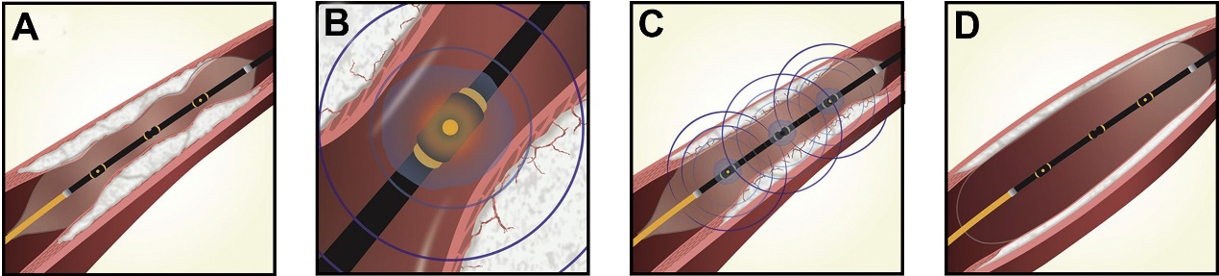

ショックウェーブ

もともと腎・尿管結石に使用されていた体外衝撃波治療を応用し、血管内でカテーテルを通じて衝撃波を発生することにより、石灰化を破砕してステントが十分拡張することが出来るようになります。治療に伴う合併症が極めて少ないという特徴があります。

Kereiakes DJ, et al. Principles of Intravascular Lithotripsy for Calcific Plaque Modification. JACC Cardiovasc Interv. 2021;14:1275–1292.より引用